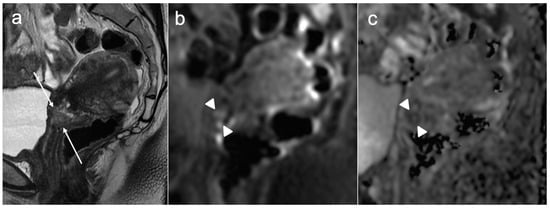

6. FIGO Stage III

- Avesani, G.; Perazzolo, A.; Amerighi, A.; Celli, V.; Panico, C.; Sala, E.; Gui, B. The Utility of Contrast-Enhanced Magnetic Resonance Imaging in Uterine Cervical Cancer: A Systematic Review. Life 2023, 13, 1368. [Google Scholar] [CrossRef] [PubMed]

- Akita, A.; Shinmoto, H.; Hayashi, S.; Akita, H.; Fujii, T.; Mikami, S.; Tanimoto, A.; Kuribayashi, S. Comparison of T2-weighted and contrast-enhanced T1-weighted MR imaging at 1.5 T for assessing the local extent of cervical carcinoma. Eur. Radiol. 2011, 21, 1850–1857. [Google Scholar] [CrossRef]

- Ciulla, S.; Celli, V.; Aiello, A.A.; Gigli, S.; Ninkova, R.; Miceli, V.; Ercolani, G.; Dolciami, M.; Ricci, P.; Palaia, I.; et al. Post treatment imaging in patients with local advanced cervical carcinoma. Front. Oncol. 2022, 12, 1003930. [Google Scholar] [CrossRef]

- Pötter, R.; Tanderup, K.; Schmid, M.P.; Jürgenliemk-Schulz, I.; Haie-Meder, C.; Fokdal, L.U.; Sturdza, A.E.; Hoskin, P.; Mahantshetty, U.; Segedin, B.; et al. MRI-guided adaptive brachytherapy in locally advanced cervical cancer (EMBRACE-I): A multicentre prospective cohort study. Lancet Oncol. 2021, 22, 538–547. [Google Scholar] [CrossRef]

- Tanderup, K.; Viswanathan, A.; Kirisits, C.; Frank, S.J. MRI-guided brachytherapy. Semin. Radiat. Oncol. 2014, 24, 181–191. [Google Scholar] [CrossRef]

- Russo, L.; Lancellotta, V.; Miccò, M.; Fionda, B.; Avesani, G.; Rovirosa, A.; Wojcieszek, P.; Scambia, G.; Manfredi, R.; Tagliaferri, L.; et al. Magnetic resonance imaging in cervical cancer interventional radiotherapy (brachytherapy): A pictorial essay focused on radiologist management. J. Contemp. Brachytherapy 2022, 14, 287–298. [Google Scholar] [CrossRef] [PubMed]